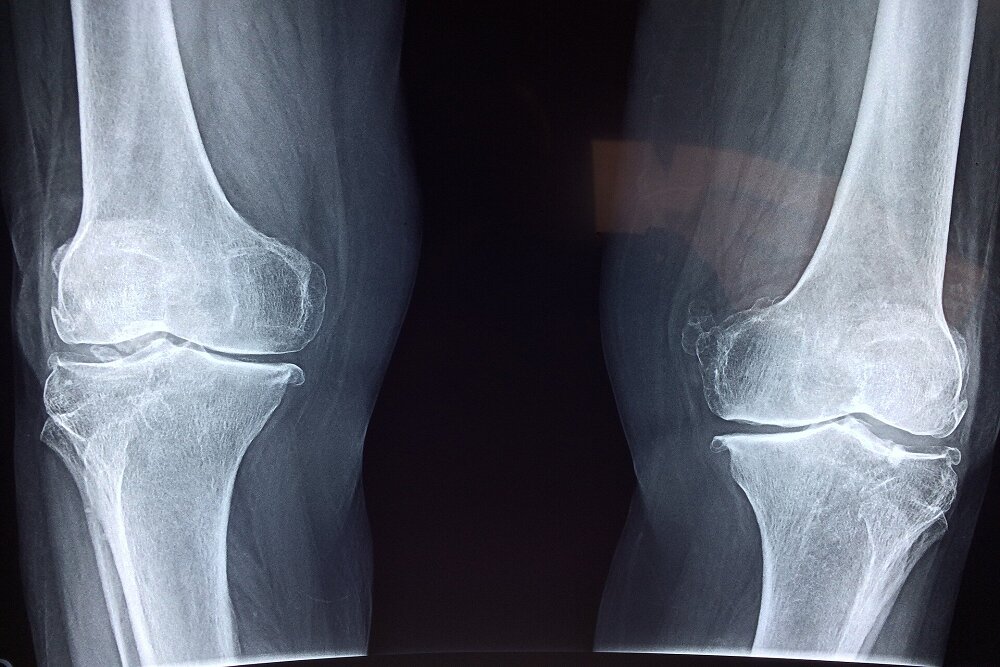

آسیب به استخوانها

نخستین نگرانی، تاثیر منفی بر سلامت استخوانهاست. مصرف نوشابه و الکل هر دو با کاهش تراکم مواد معدنی استخوان و افزایش خطر شکستگی مرتبط است. مصرف نوشابه بهدلیل وجود اسید فسفریک میتواند تعادل کلسیم و فسفر را بر هم بزند و خطر شکستگی لگن را افزایش دهد. مصرف الکل نیز با کمبود کلسیم، اختلالهای کبدی و کاهش ویتامین دی همراه است که همگی به تضعیف استخوانها منجر میشوند.